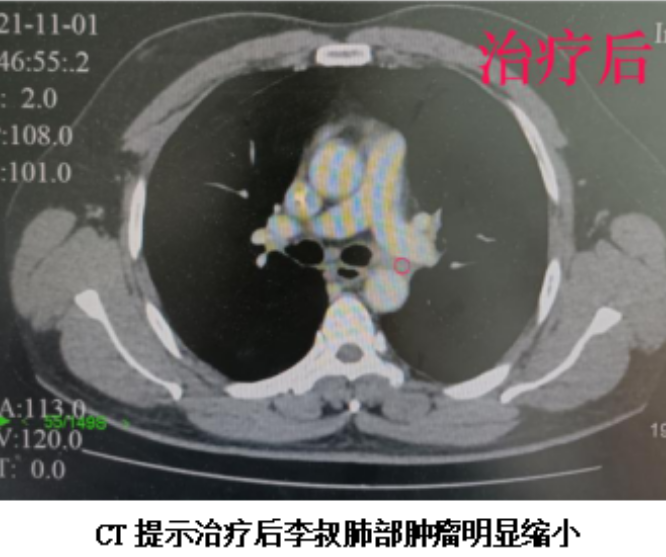

复查CT结果显示,李叔肺部的肿瘤已从5.0cm*4.4cm*4.6cm缩小到2.0*1.1*1.0cm,体积奇迹般缩小了90%以上!肺门纵膈淋巴结也明显缩小。复查PET/CT检查提示原为阳性的对侧肺门淋巴结,在治疗后转阴。